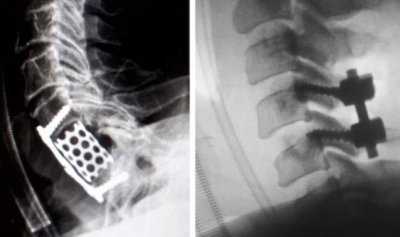

O tratamento cirúrgico para as fraturas da coluna é reservado para uma minoria dos casos. Ele está indicado nas lesões instáveis ou que apresentam lesão neurológica associada. Existem diversas opções de tratamento cirúrgico, desde procedimentos minimamente invasivos (fixações percutâneas, cifoplastia, etc…) até procedimentos abertos tradicionais (artrodese anterior, artrodese posterior, etc…). O tipo de tratamento cirúrgico necessário para cada caso deve ser indicado por um médico especializado.

Após o procedimento, a recuperação dependerá da extensão da cirurgia, uma vez que isto é avaliado pelo ortopedista de coluna durante o acompanhamento inicial do paciente.

Caso seja minimamente invasiva, o processo de reabilitação consiste em sessões de fisioterapia para a recuperação de força muscular, além de trabalhos posturais, que auxiliem no dia a dia do paciente.

No entanto, em cirurgias com um grau mais elevado de complexidade, é preciso de um período de repouso, assim como a avaliação mensal de um ortopedista de coluna, combinada com o acompanhamento fisioterapêutico para a reabilitação correta.